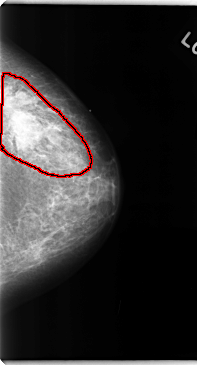

C_0108_1.LEFT_MLO

LEFT_MLO LINES 4760 PIXELS_PER_LINE 2656 BITS_PER_PIXEL 12 RESOLUTION 50 OVERLAY

FILE: C_0108_1.LEFT_MLO.OVERLAY

TOTAL_ABNORMALITIES 1

ABNORMALITY 1

LESION_TYPE MASS SHAPE IRREGULAR MARGINS ILL_DEFINED

ASSESSMENT 5

SUBTLETY 5

PATHOLOGY MALIGNANT

TOTAL_OUTLINES 1

BOUNDARY